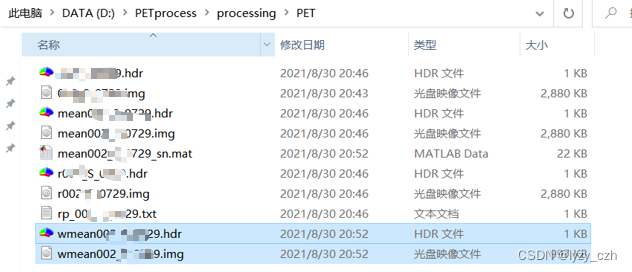

转换完成后输出如下:

这里生成了多个hdr/img的图像,只需要选择其中最好的一个即可(我看起来都是一样的)

此时在输出目录下生成如下文件:

生成如下文件:

生成如下文件: